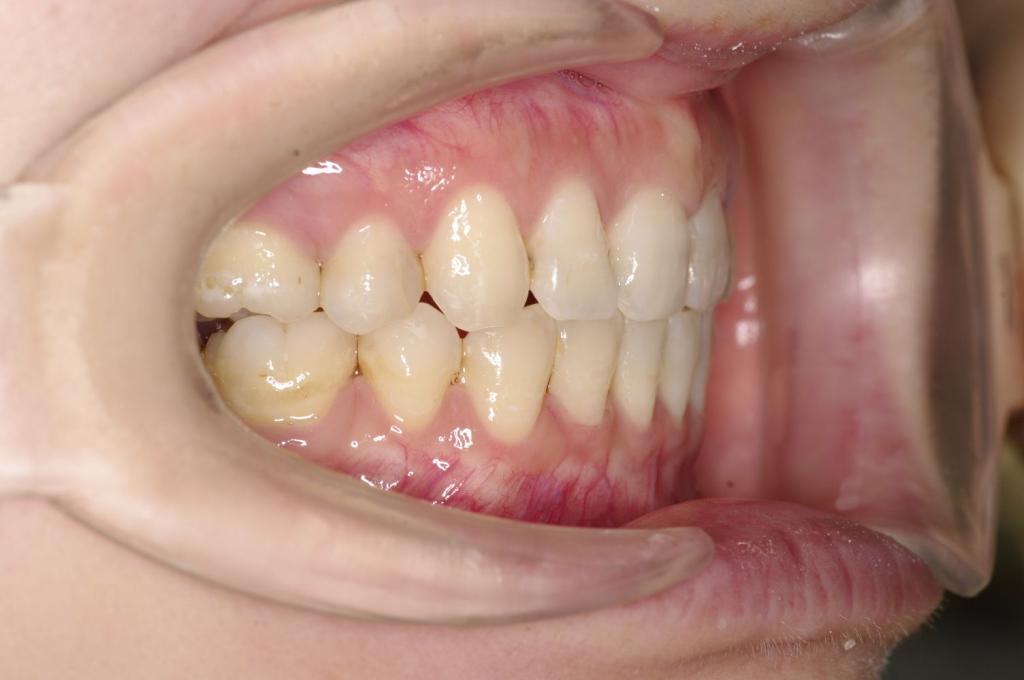

前歯、出っ歯・開咬の矯正治療

(治療期間、治療前後写真、治療方法、費用)WORKS